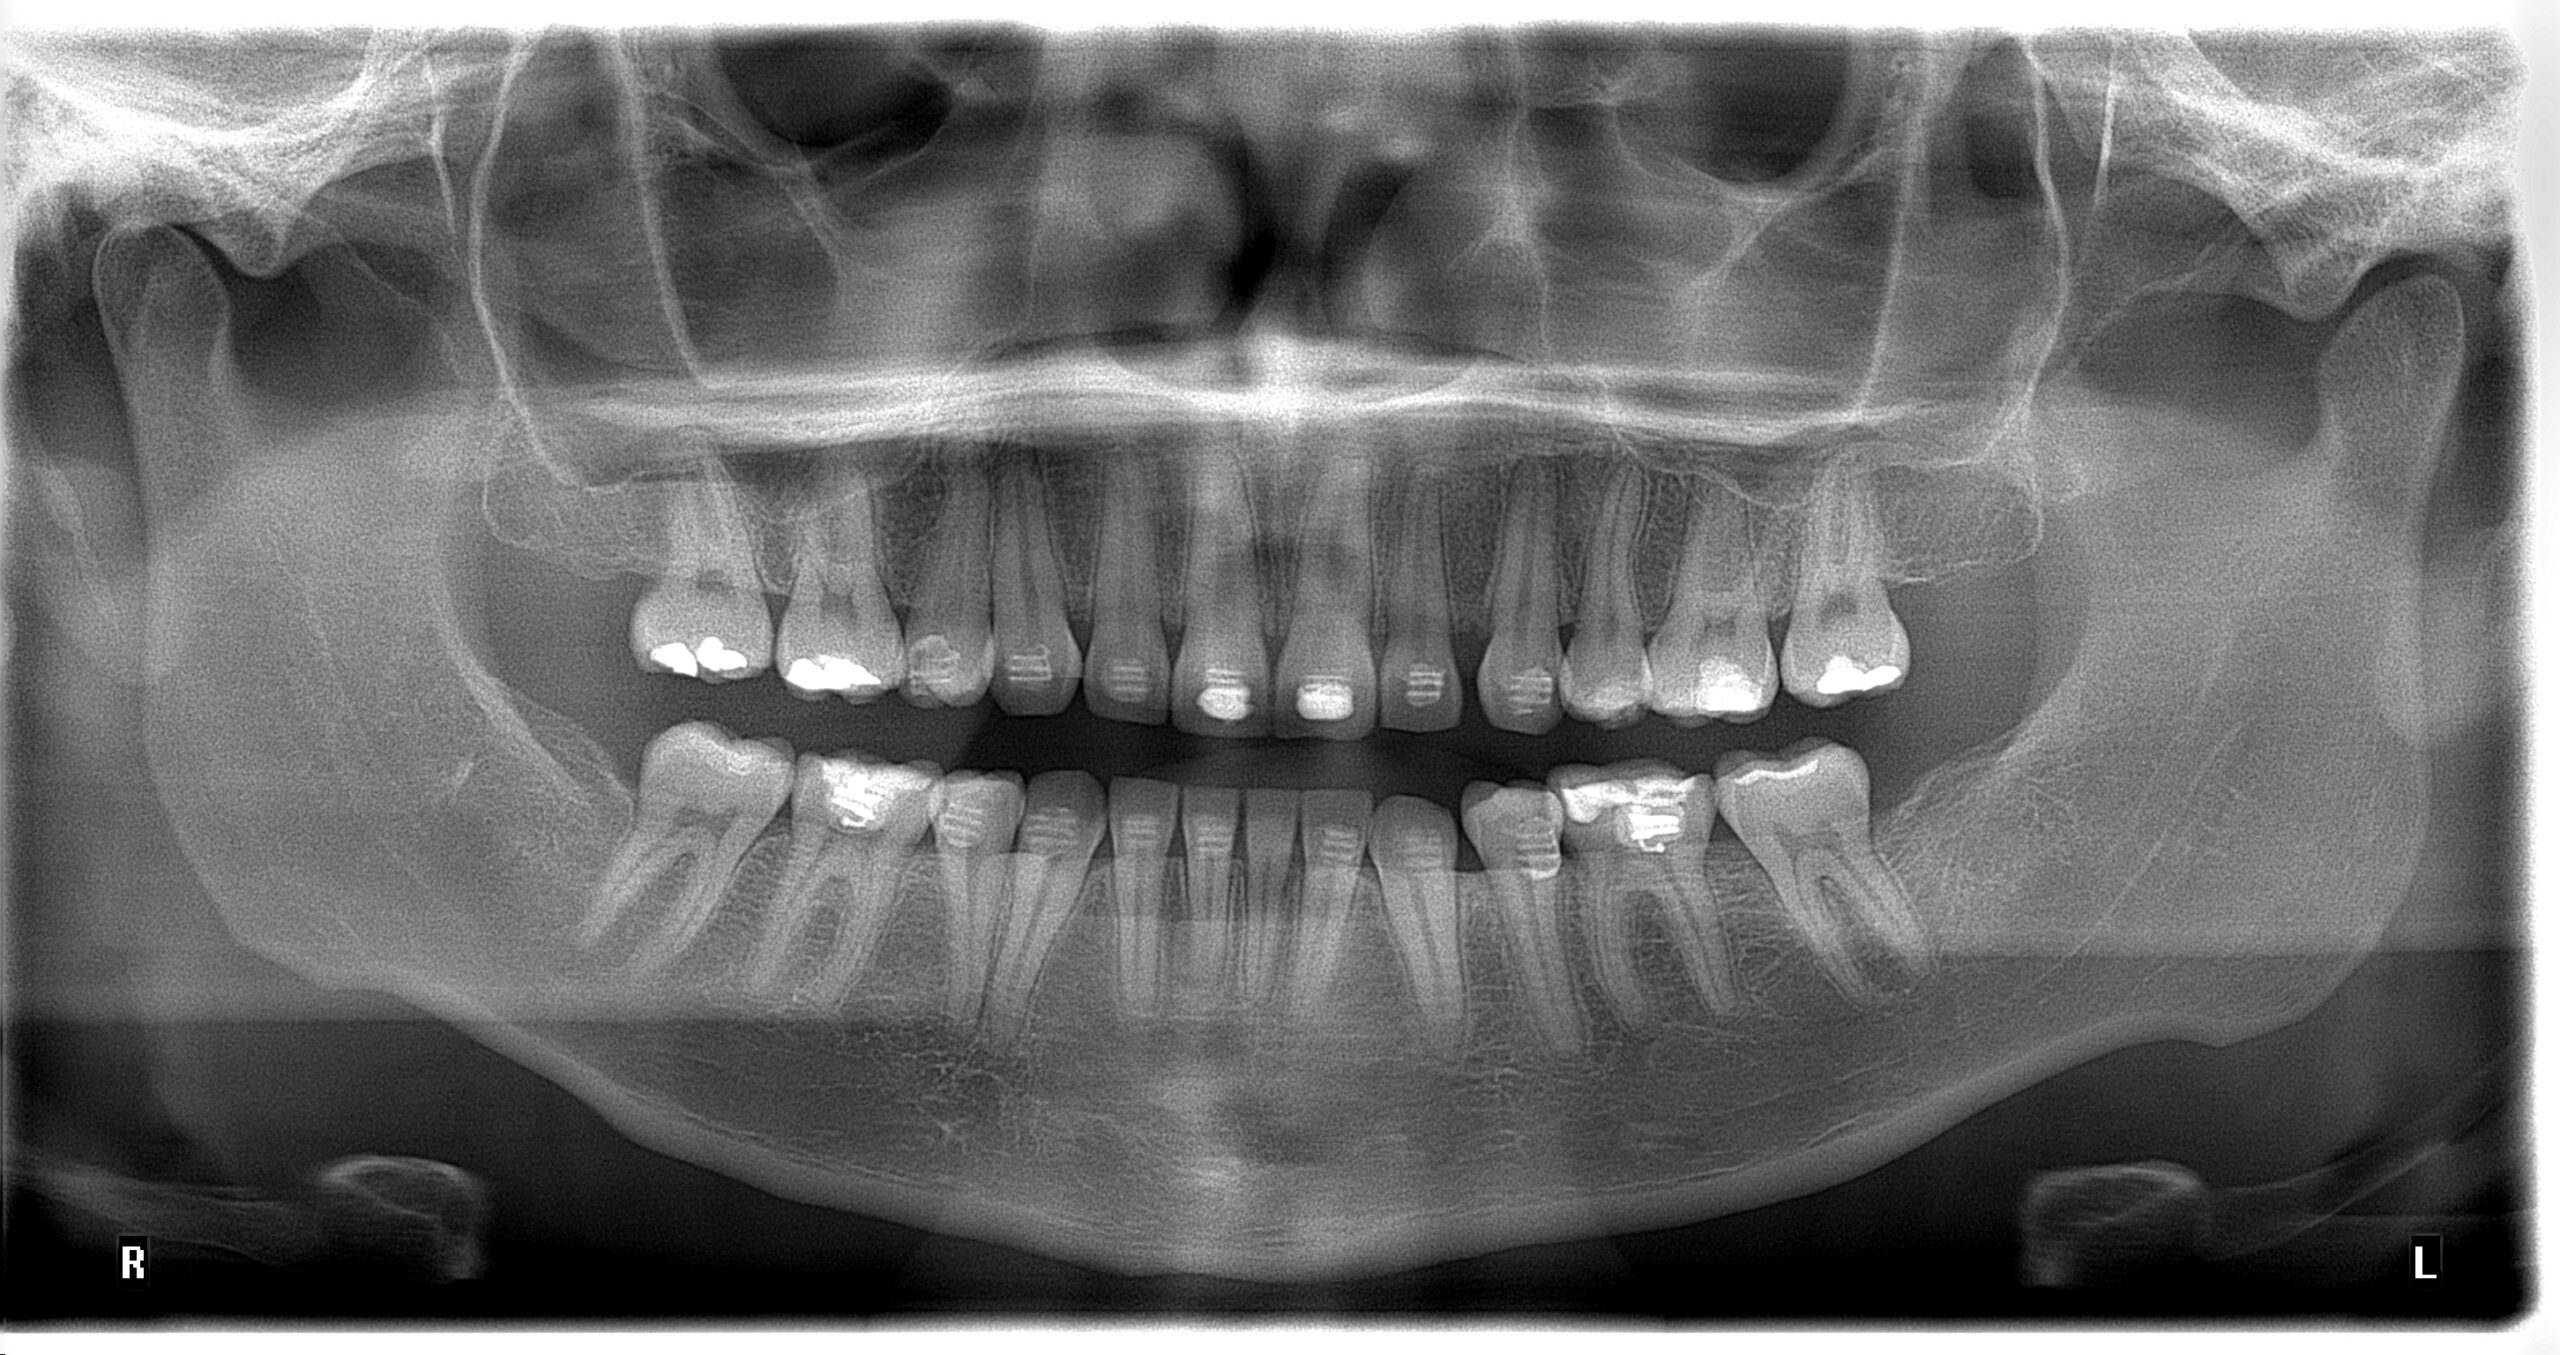

Radiografía panorámica dental en Medellín: La panorámica dental en Medellín es utilizada para tener una visión general del paciente ya que es posible evaluar en conjunto los dientes, el hueso alveolar, los maxilares y las estructuras anatómicas adyacentes, dando una visión detallada de la salud general del paciente

La radiografía panorámica ofrece una vista general del paciente, permitiendo evaluar dientes, hueso alveolar, maxilares y estructuras adyacentes para un diagnóstico integral.